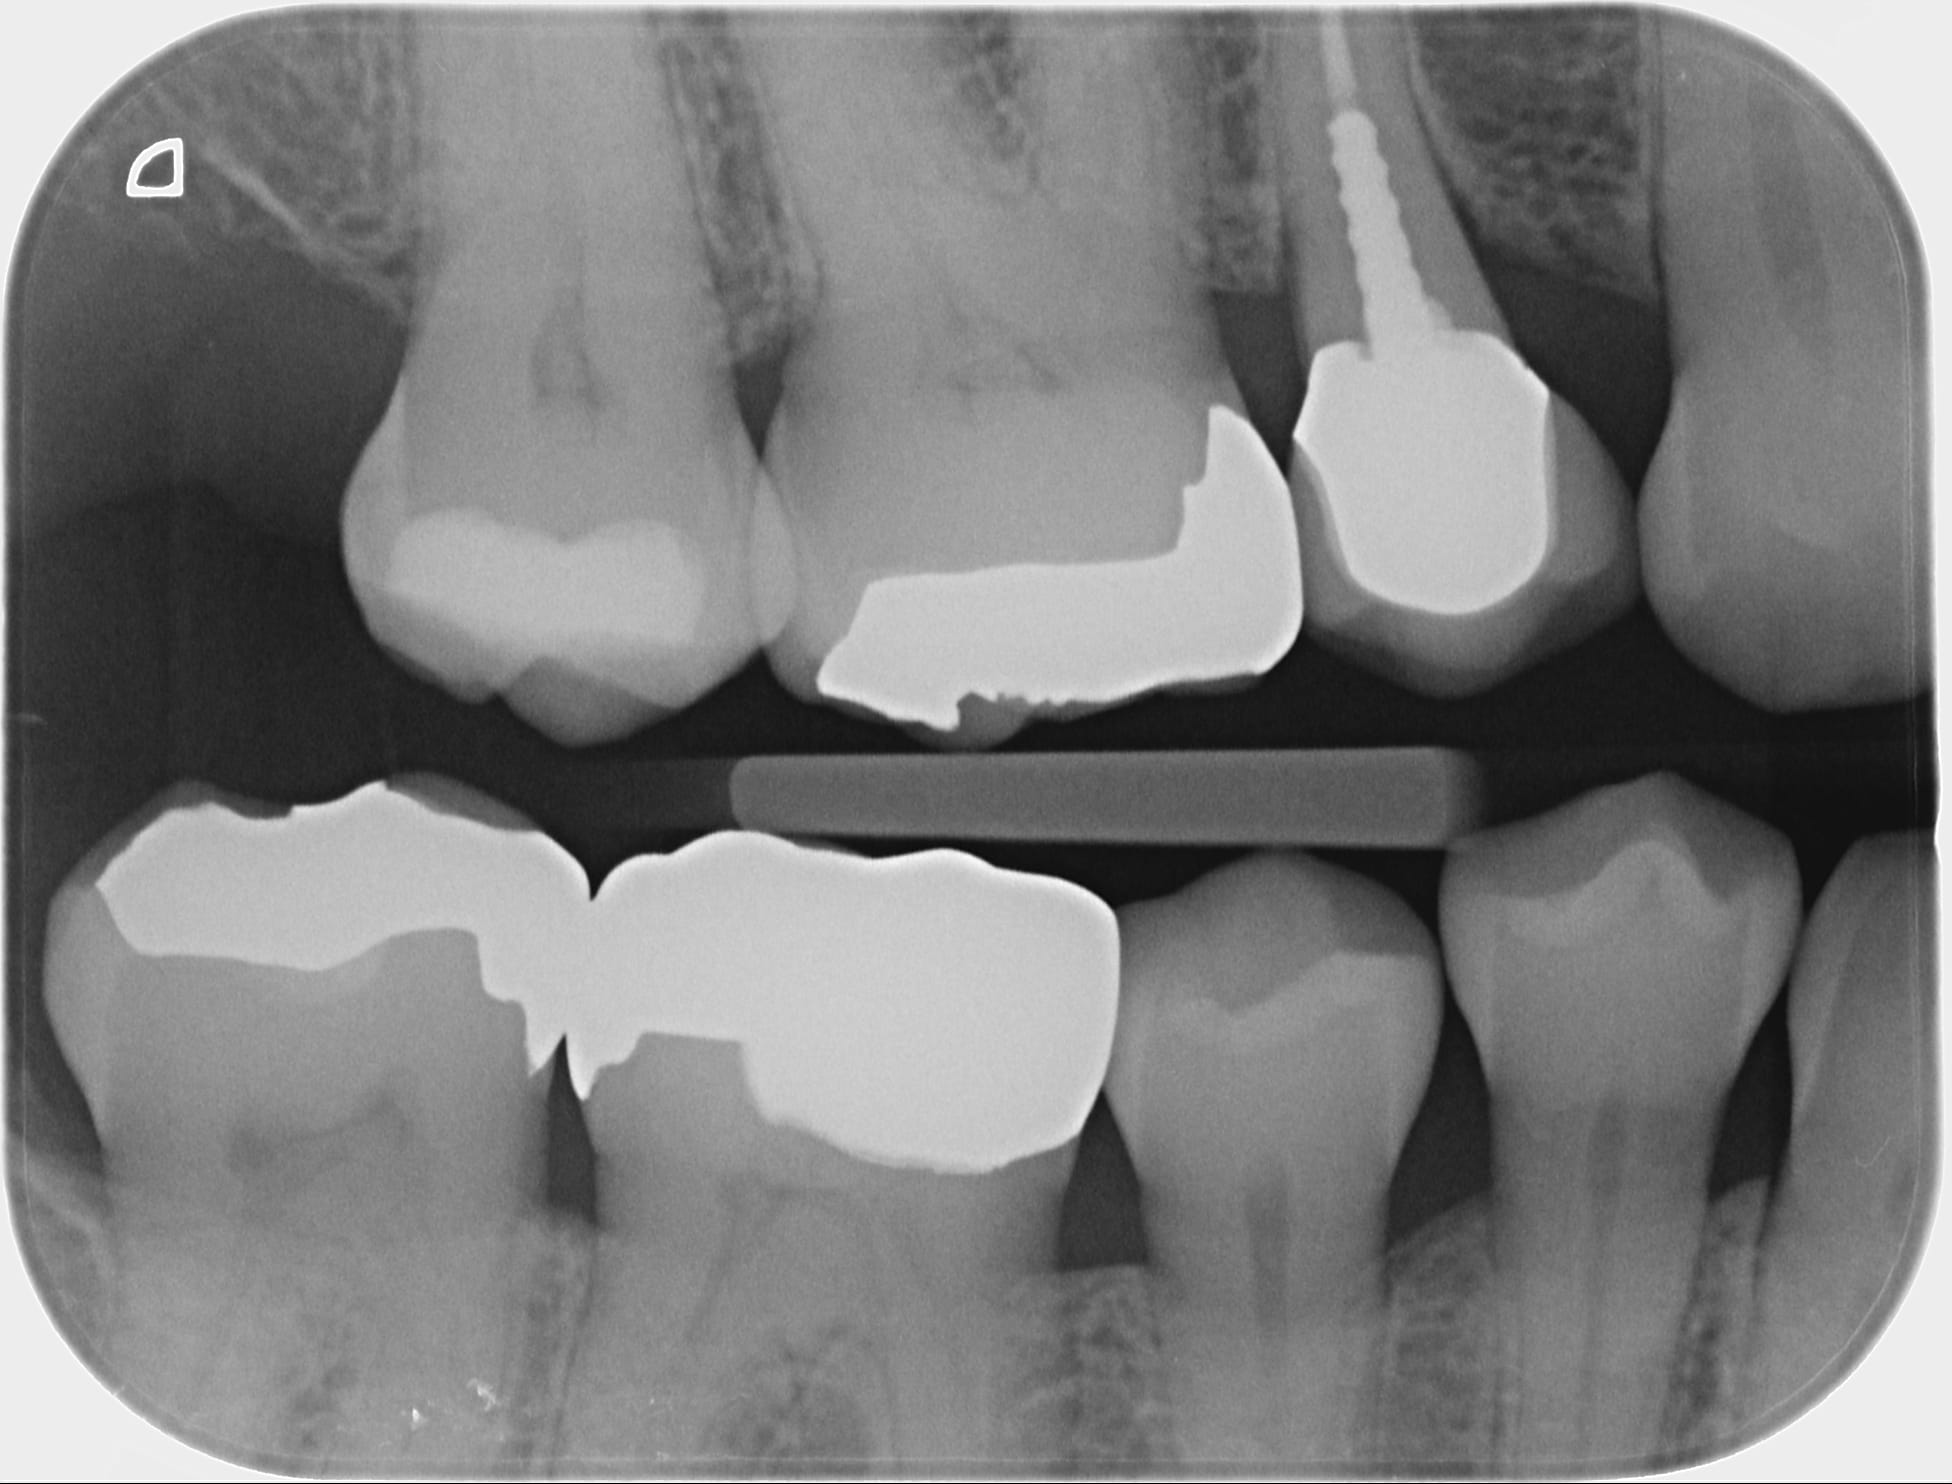

> > Heureusement qu'elle reste tranquille cette dent, j'aimerais pas à avoir à lui

> > Au vu de la préop, ça motive pour garder vivante ;)

> Par contre, c'est vrai que l'endo en seconde intention sera compliqué.

Je me suis fait la même réflexion mais la dent n'a pas l'air plus calcifié maintenant qu'en pré opératoire donc tu n'aurais rien à te reprocher. Beau boulot et merci pour le partage.